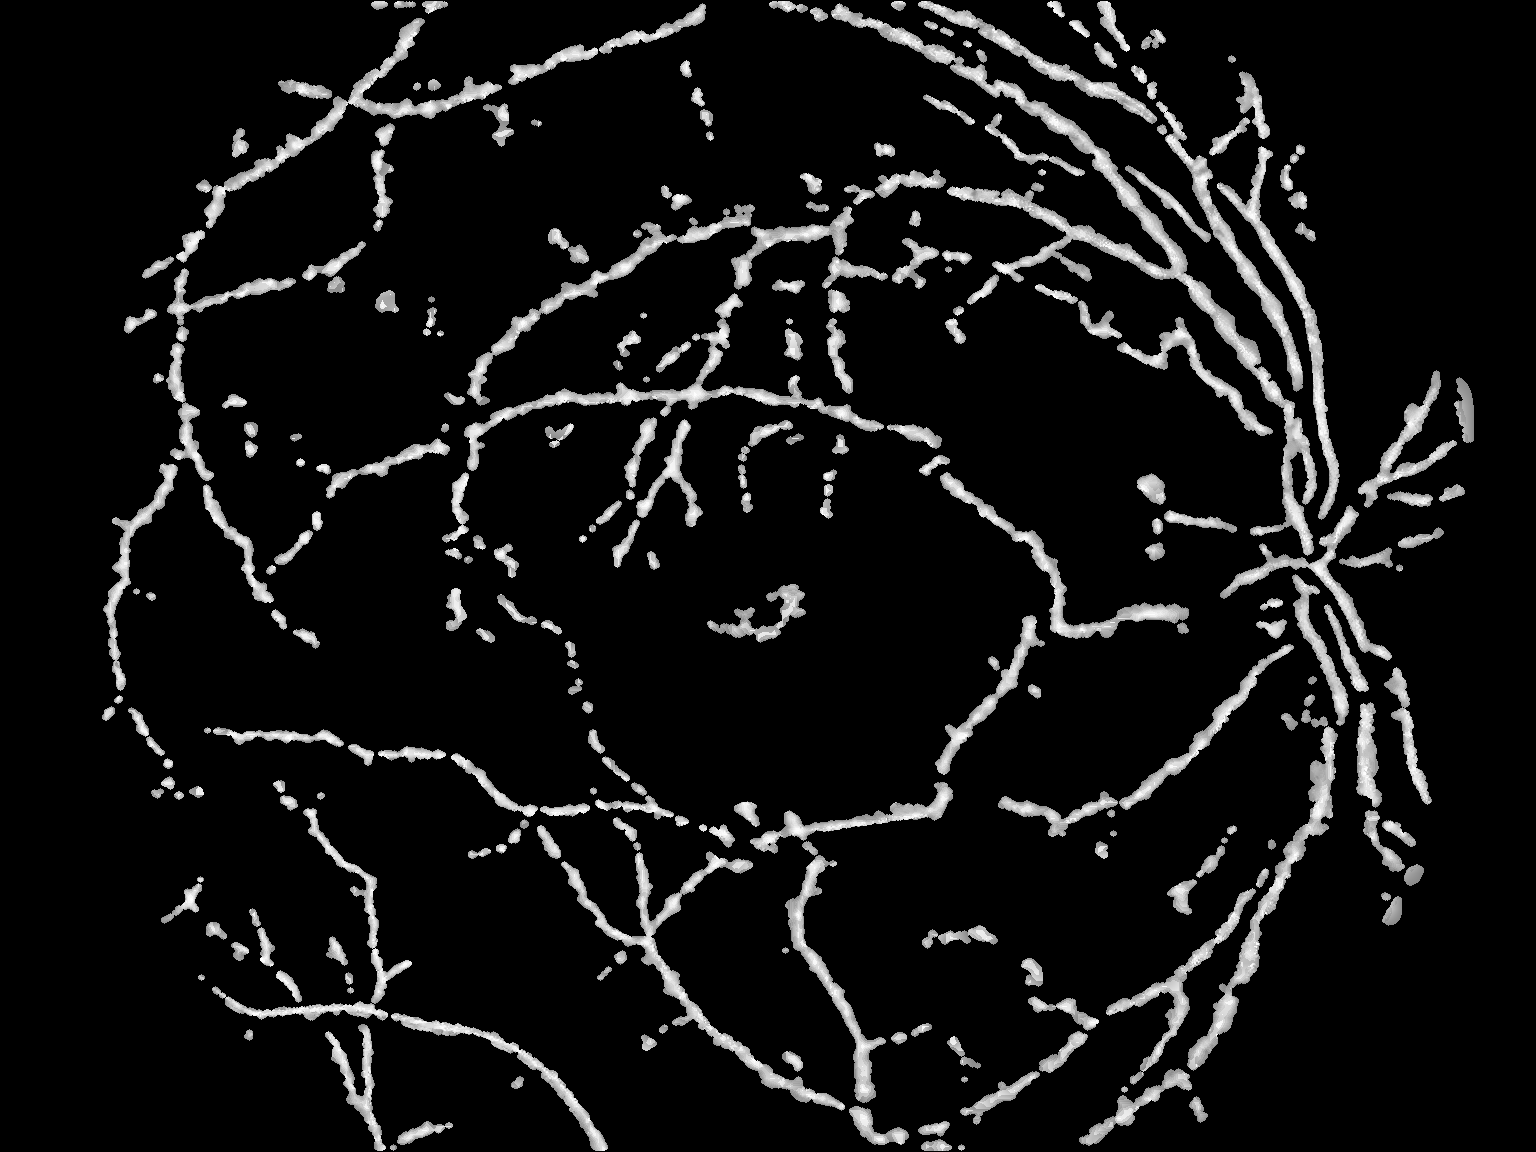

结果

这绝不是最优的,但我认为它应该为您提供足够的启动工具。

如何:高通(图像减去高斯平滑与西格玛12),然后阈值(126),然后小目标抑制(小于300个像素的对象被删除)?

(我用了你的上一张照片)